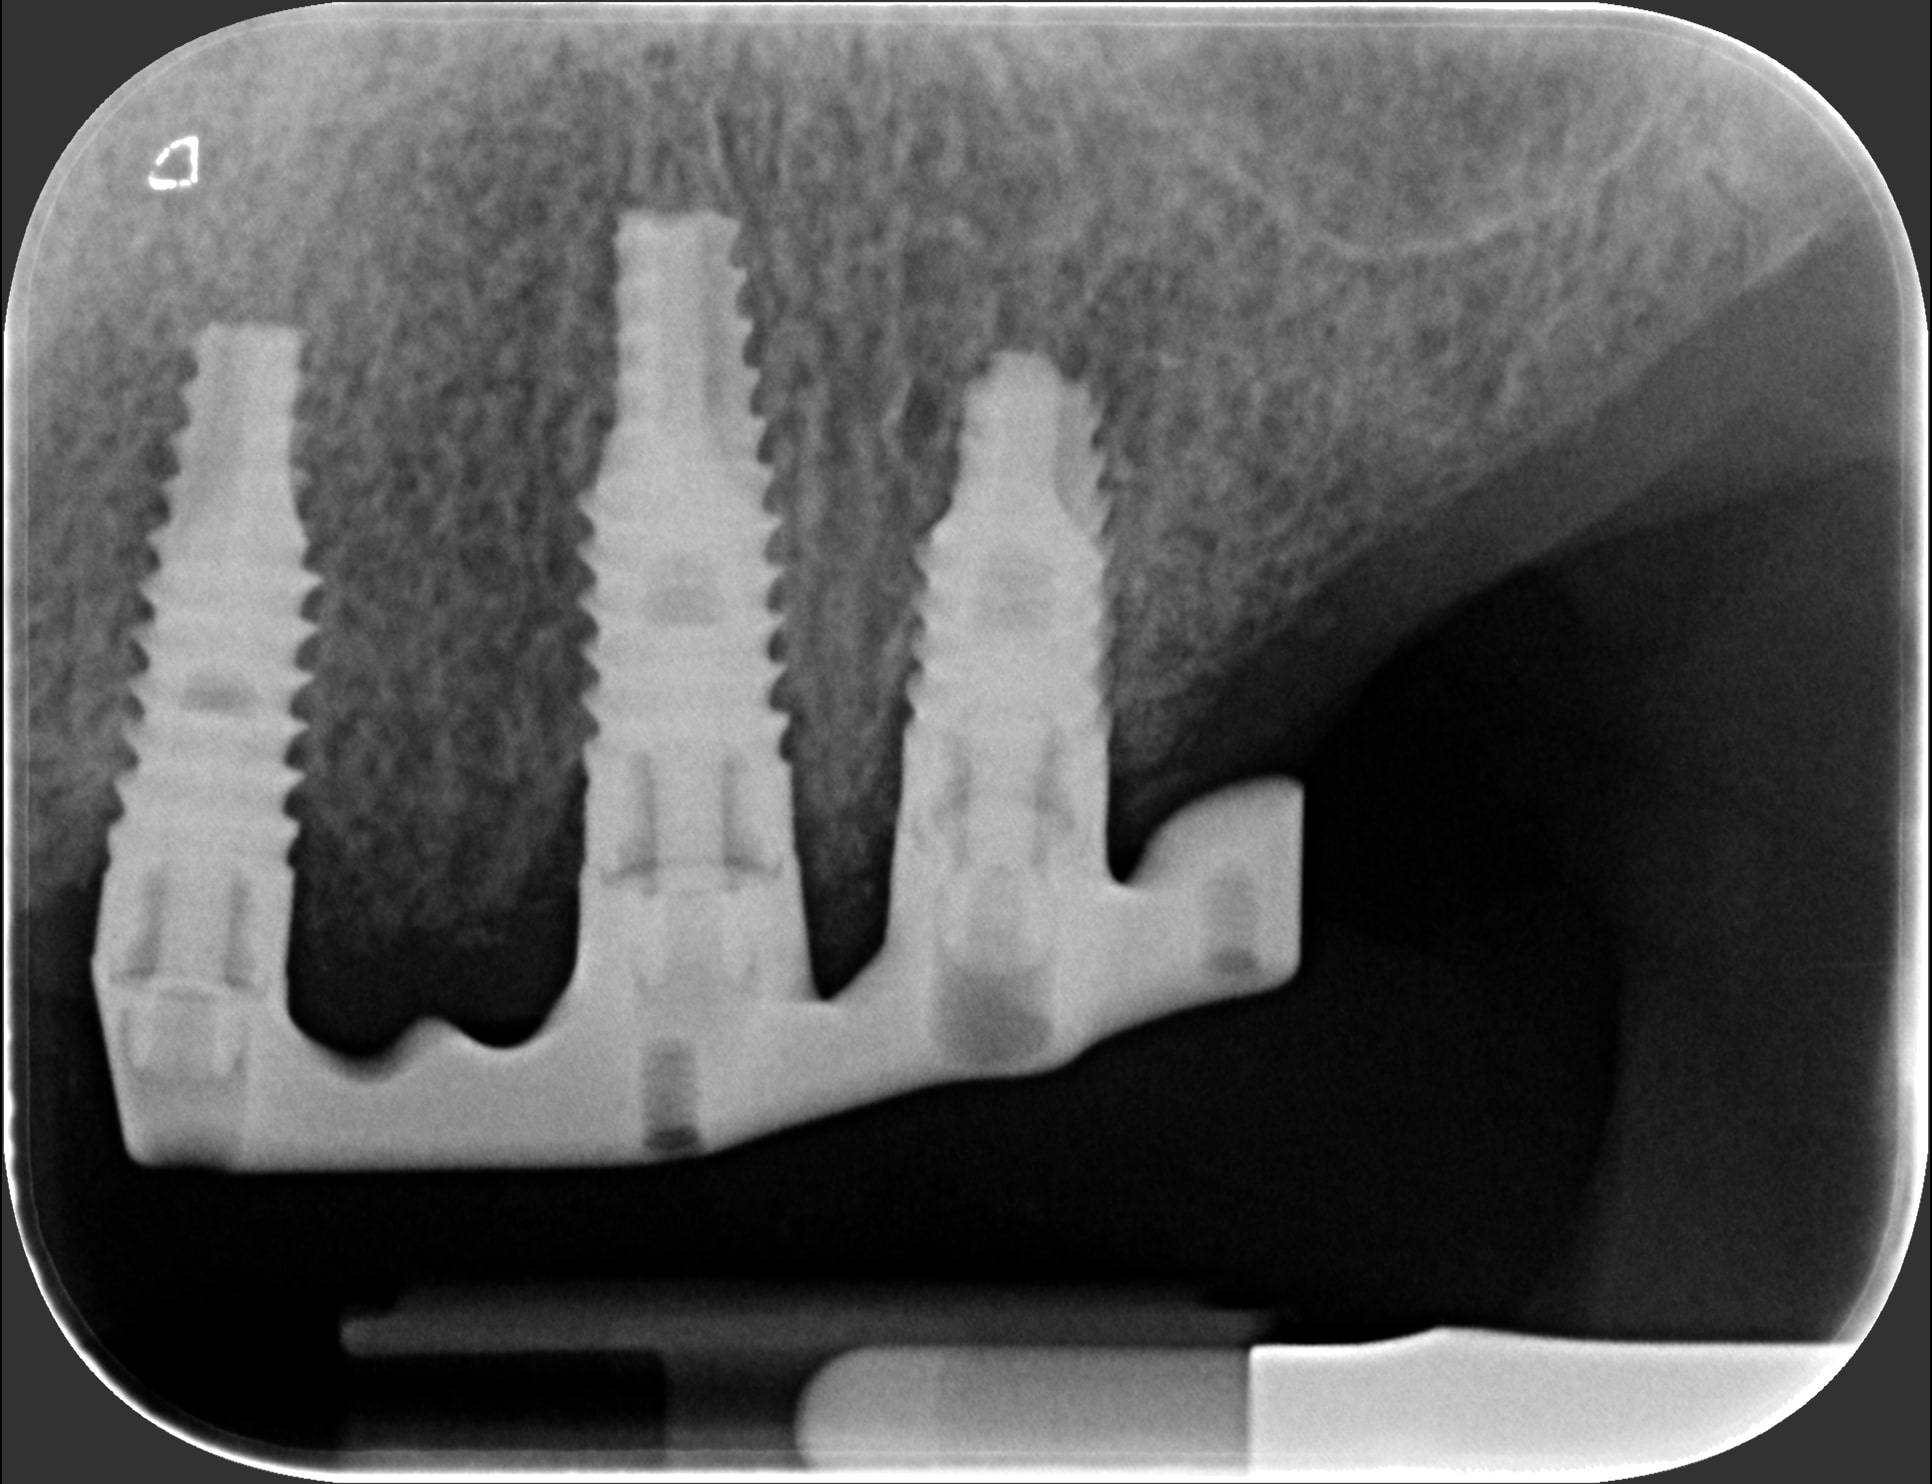

Generalmente devono trascorrere alcuni mesi tra l’intervento chirurgico di inserimento di un impianto e la realizzazione della protesi da fissare ad esso.

In questo lasso di tempo, nel quale l'impianto è sommerso sotto la gengiva e si avvia il processo di guarigione ossea, si realizza l'osteointegrazione, ovvero un intimo contatto fra l’osso e la superficie biocompatibile in titanio dell’impianto.

Tuttavia, in alcuni casi selezionati, è possibile protesizzare gli impianti subito dopo il loro posizionamento, nel giro di pochi giorni o addirittura nel corso della stessa seduta: questa tecnica è definita “carico immediato” e consente al paziente di entrare in Studio con la sua vecchia dentiera e di uscire il giorno stesso con una protesi fissa.

Una tecnica recente e molto apprezzata è l’implantologia computer guidata. L’anatomia della zona da operare è studiata con la Tomografia Computerizzata, simulando al computer, con un software di alta precisione 3D, il posizionamento degli impianti. Sulla base dei dati elaborati dal software si realizza in laboratorio una mascherina chirurgica che guiderà gli strumenti e gli impianti nella corretta posizione nell’osso del paziente, rendendo l’intervento più sicuro e veloce.